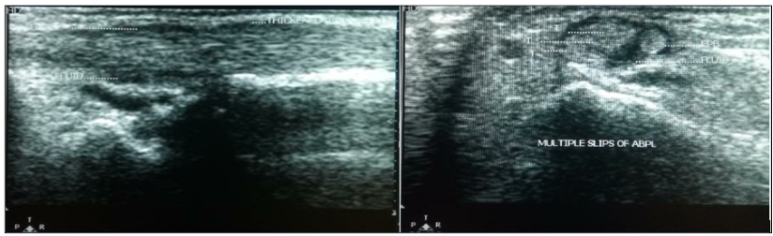

DOI: http://dx.doi.org/10.18203/2320-6012.ijrms20173989 이 '벽'이 있으면 주사 치료를 할 때 약물이 벽에 막혀 반대편 힘줄까지 도달하지 못합니다. 직접 눈으로 보지 않고 Blind 주사를 놓으면 효과가 반감될 수밖에 없는 구조적인 이유가 있었던 겁니다. 셋째, 더 놀라운 건, 환자의 60%에서 장무지외전근(APL) 힘줄이 한 가닥이 아니라 여러 가닥(Multiple slips)으로 갈라져 있었다는 점입니다.

DOI: http://dx.doi.org/10.18203/2320-6012.ijrms20173989 힘줄이 여러 갈래면 마찰이 더 심해지고 치료 난이도도 높아지겠죠. 이 논문에서도 강조하듯이 초음파는 이 해부학적 변이를 찾아내는 데 탁월합니다. 단순히 "염증입니다"가 아니라, **"힘줄에 칸막이가 있어서 염증이 고립되어 있네요"혹은"힘줄이 여러 갈래라 마찰이 심하네요"*라고정확히 구조를 파악할 수 있는거죠.